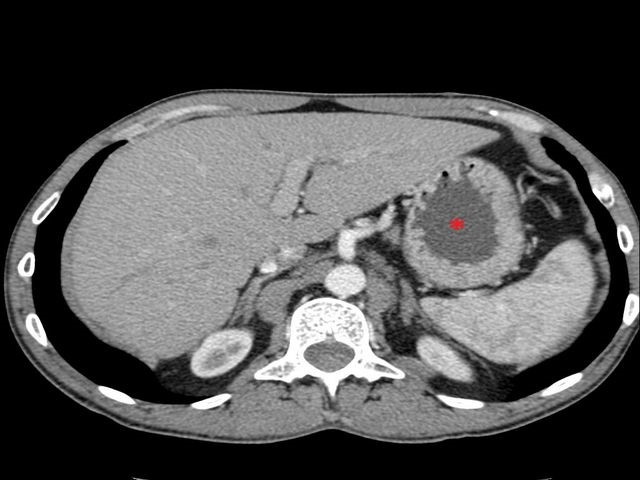

Компьютерная томография

Этот метод диагностики заключается в исследовании желудочно-кишечного тракта с помощью томографа, который использует рентгеновские лучи. Процедура проходит следующим образом: пациент располагается на столе томографа, где его облучают рентгеновскими импульсами. Чем плотнее ткань, тем меньше рентгеновских лучей проходит через нее, что позволяет выявить патологические изменения в органах, такие как опухоли, уплотнения и эрозии. Темные и четкие участки на снимках могут указывать на наличие полипов, в то время как светлые области свидетельствуют об отсутствии новообразований.

Принцип работы томографа заключается в его вращении, которое позволяет делать снимки срезов тканей и выводить результаты на экран. Однако у этого метода есть значительные недостатки: он не позволяет обнаружить мелкие патологии, а также перед диагностикой требуется введение трубки для перфораций.

Данный метод противопоказан для беременных женщин и пациентов с избыточным весом. Кроме того, стоит отметить, что исследование связано с повышенным уровнем рентгеновского облучения.

Компьютерная томография не является высокоинформативным методом и используется преимущественно для предварительной диагностики. Если в ходе исследования обнаруживаются какие-либо патологии, пациенту могут быть назначены эндоскопическое или капсульное гастроскопирование для более детального анализа.